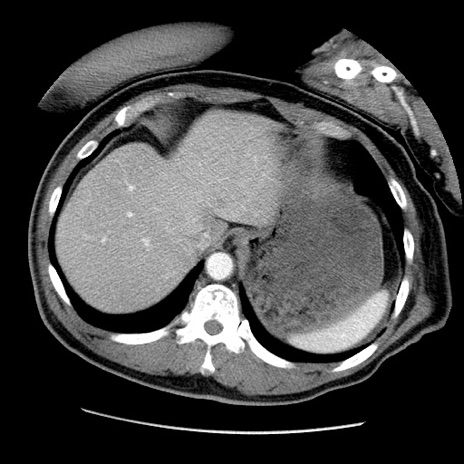

症例22(横断像)

【症例】50歳代男性

【主訴】腹痛

【現病歴】AVMからの被殻出血のため回復期リハ病棟入院中。 本日午後3時頃急に下腹部痛が出現した。

【既往歴】AVM、被殻出血、虫垂炎、高血圧

【身体所見】意識晴明、左半身不全麻痺、会話の理解は良好、36.5°C、腹部:膨隆、全体に板状硬、下腹部正中に圧痛点あり、反跳痛-、筋性防御不明、右下腹部にope scar

【データ】WBC 9400、CRP 0.06